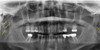

Label the following image:

1. blue: mandibular body

2. yellow: angle of mandible

3. orange: ramus of mandible

4. red: symphysis

5. green: inferior border